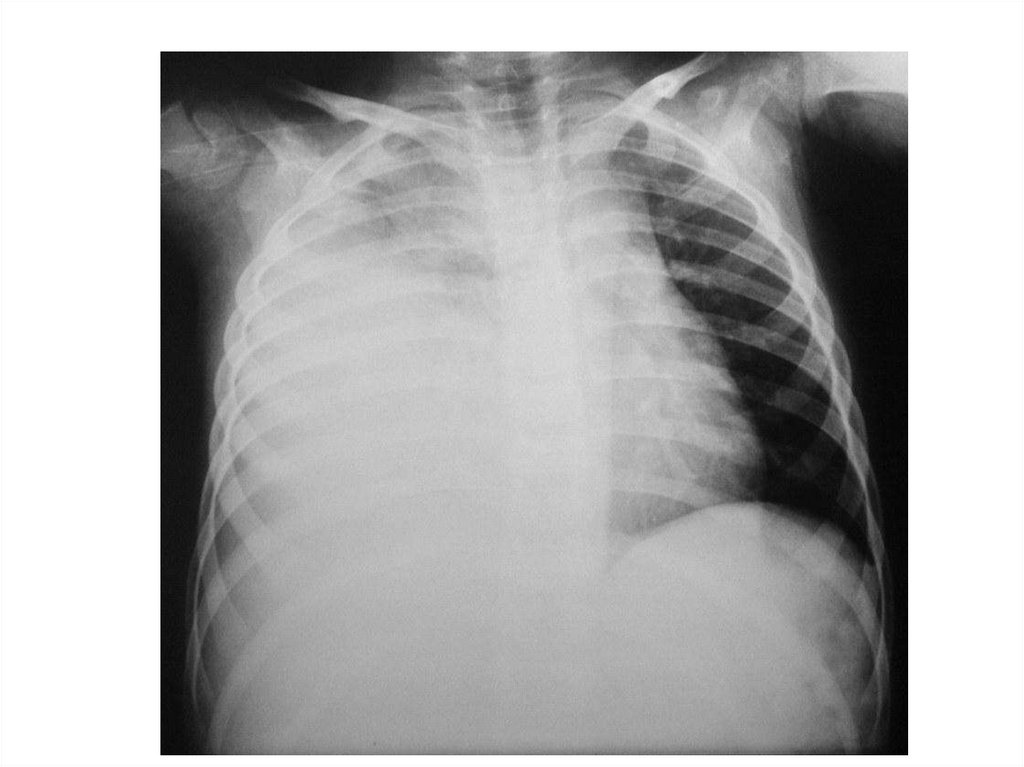

Пневмоторакс

Пневмоторакс Гидроторакс

просветление затенение